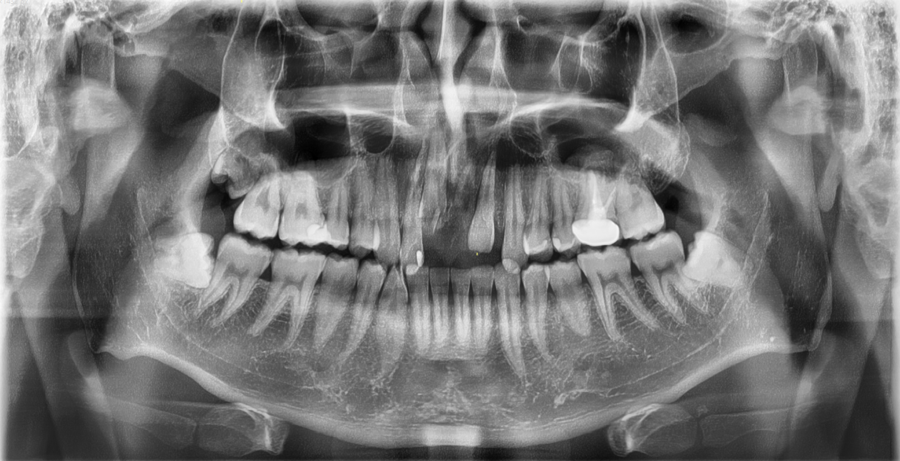

교통사고 이후 앞니가 떨어진 상태로

내원하신 환자분의 엑스레이입니다.

사고 직후뿐 아니라, 이후 경과에 따라 주변 치아와

잇몸뼈 변화가 없는지 추가 확인을 위해 촬영한 이미지입니다.

탈구된 앞니를 재위치하고 고정 장치를 이용해 치료한 사례입니다.